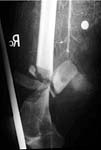

Case 2 - avulsed elbow joint with complete pulling apart of brachial artery, open wound with huge overlying skin loss. Immediate OR, brachial artery shunted, THEN Ortho puts on cross-joint ex-fix, we come back and definitively repair artery (ASVG), document patency with on table completion angio--then plastics swings lat dorsi pedicled flap thru axilla to cover.

Shunt then ex-fix

Vascular repair